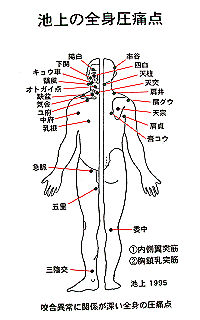

⑥池上の全身圧痛点

皮膚上を圧診して圧痛点における深部の知覚を検査し、少し痛いは1、痛いは2、すごく痛いだと3と、三段階で評価して、対応する器官の痛変の様相を測定しようとするもの。